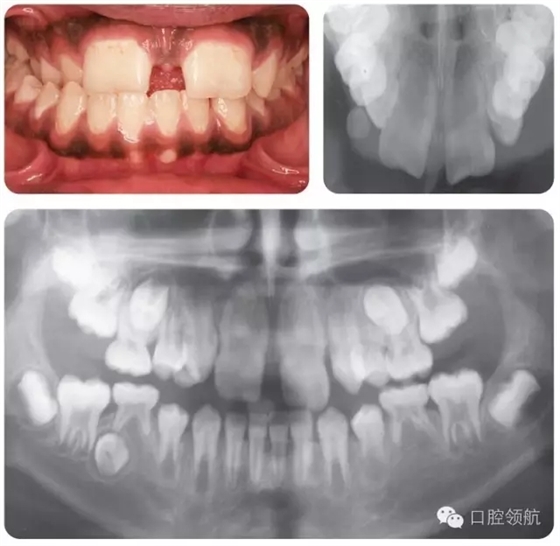

這是一個全科牙醫(yī)轉(zhuǎn)診的病例。該名女性患者I類錯牙合,輕度擁擠,LL6嚴重齲壞,無法保留。患牙有間歇性的夜間痛,使其在夜間痛醒。圖2.8是由全科牙醫(yī)提供的最近的全景片。

圖2.8

全景片上最主要的特征有哪些?

● 混合牙列。

● 切牙已萌出。

● LL6嚴重齲壞;可見遠中根根周感染,有臨時修復(fù)體存在。

● 除第三磨牙以外所有恒牙都存在(LR8可見早期牙胚發(fā)育)。

● 第二磨牙的牙冠發(fā)育完成。下頜的根間區(qū)域已開始發(fā)育。